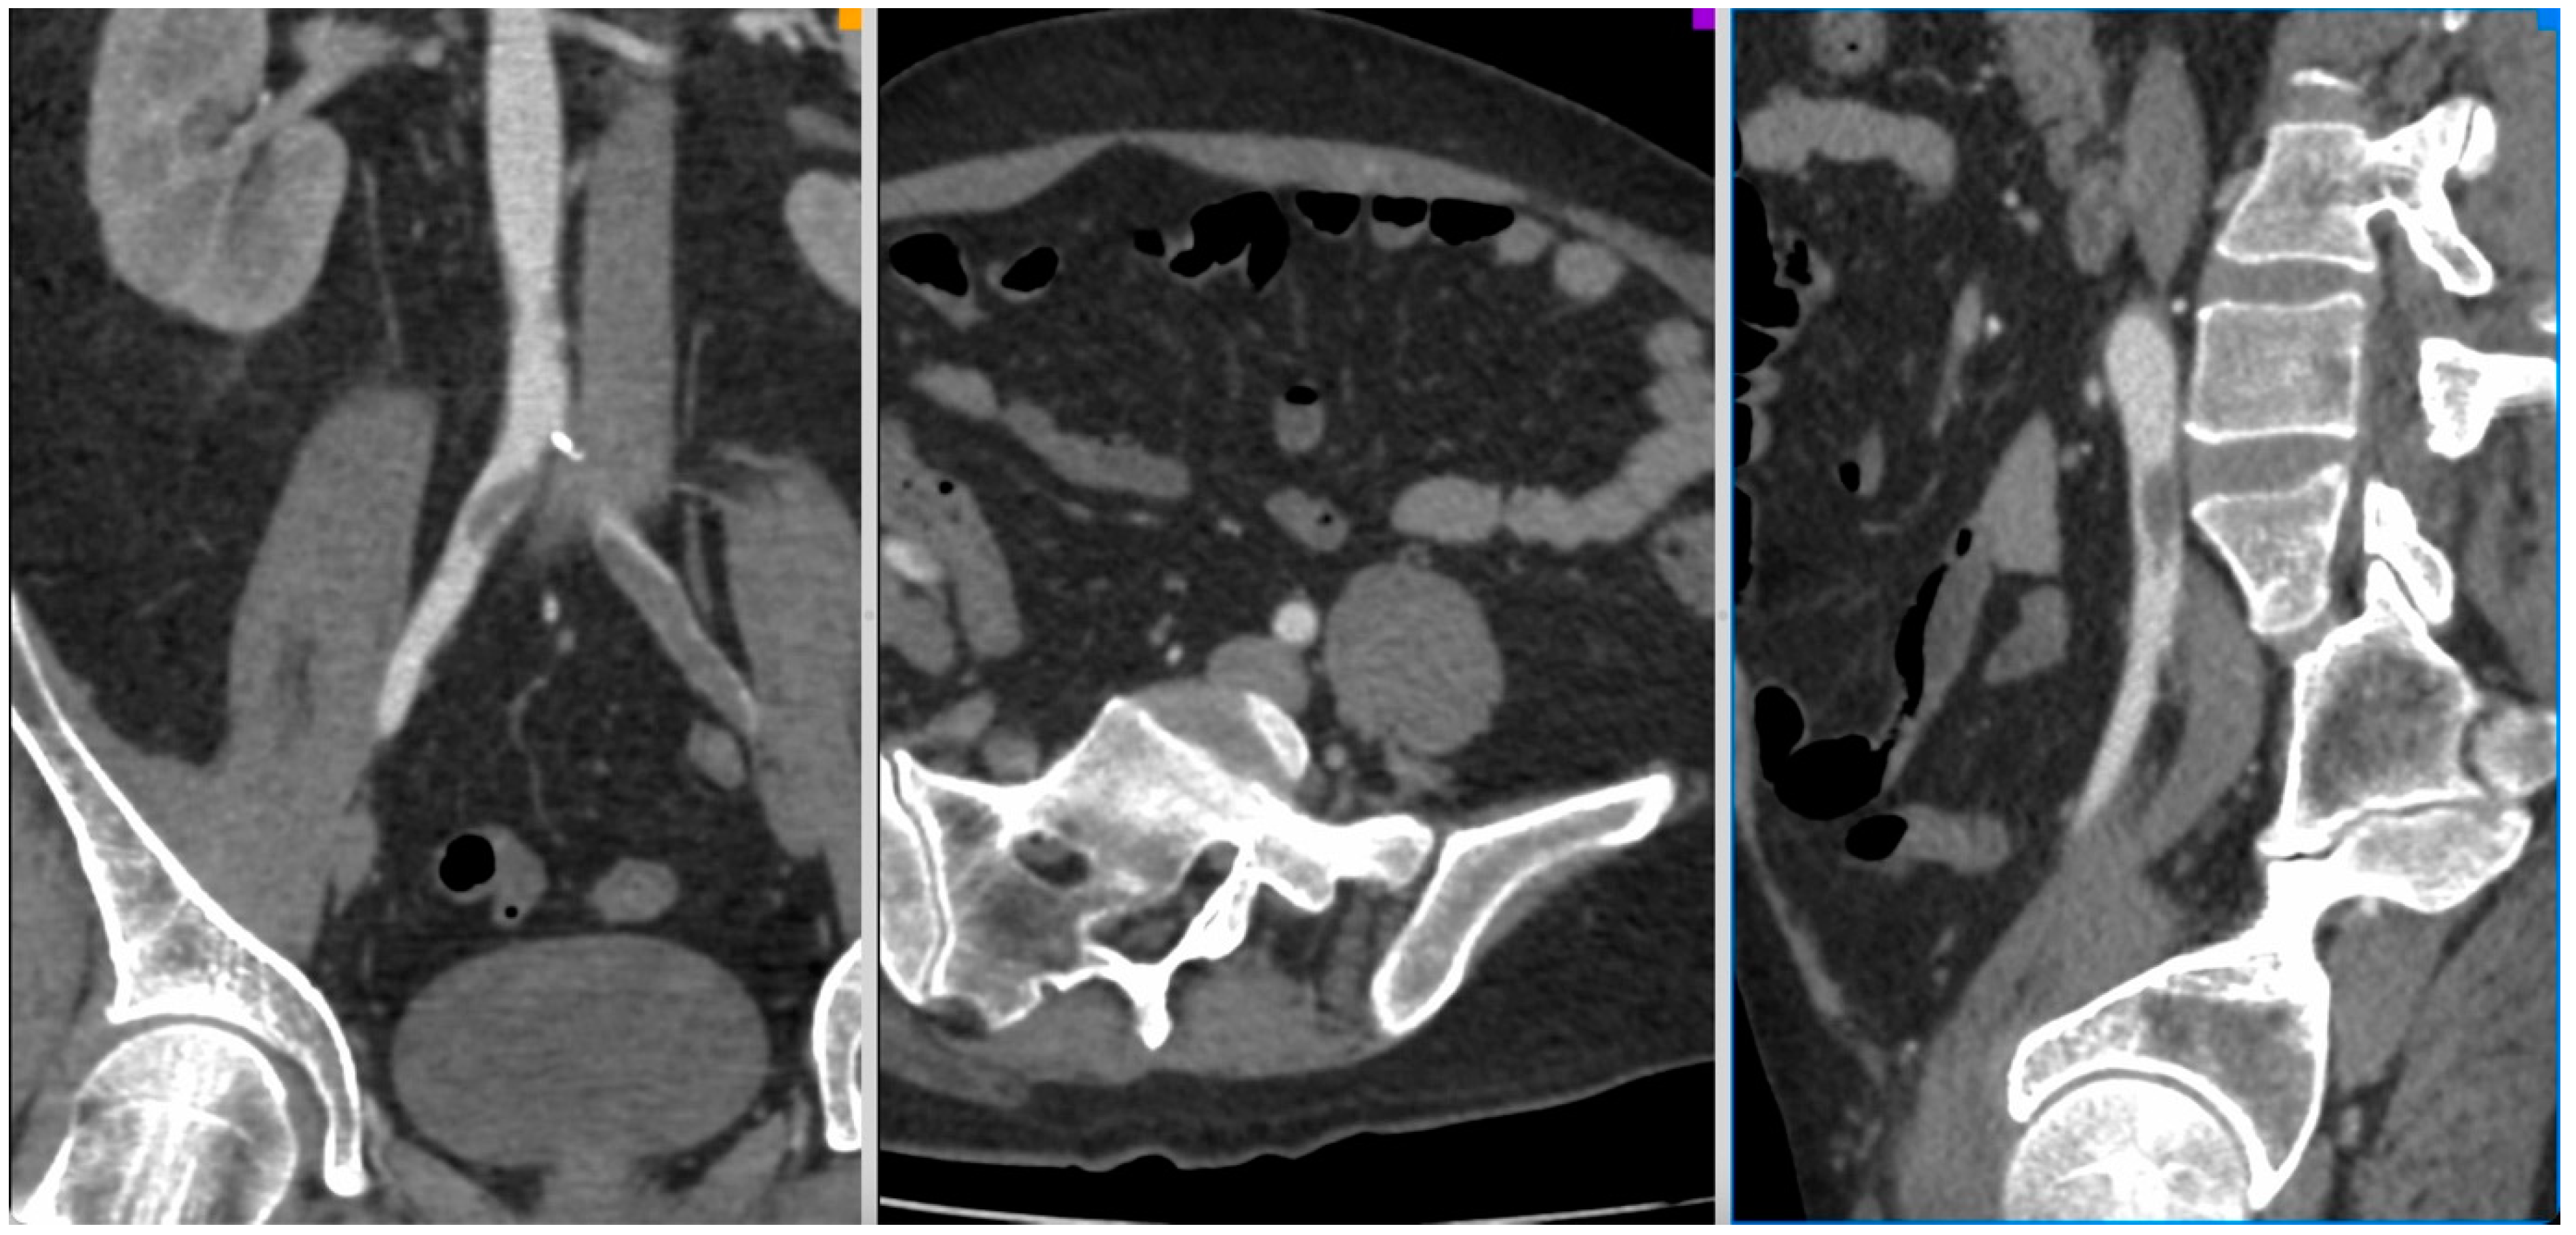

Figure 2.

CT-Angio of a 42 yo male patient with aortic and iliac thrombosis with bilateral lower limb acute ischemia IIA Rutherford, 13 days after SARS-CoV-2 diagnosis.